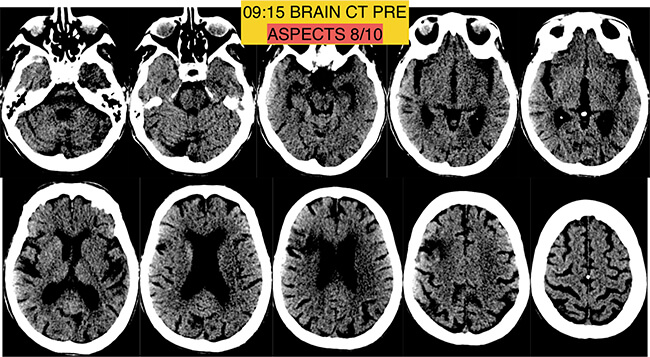

Αξονική τομογραφία-αγγειογραφία: Άμεσα μεταφέρθηκε στο ακτινολογικό και υποβλήθηκε σε αξονική τομογραφία.

Στην αρχική αξονική τομογραφία χωρίς σκιαγραφικό

δεν διαπιστώθηκε ακόμη απεικονιστικά εμφανής βλάβη στον εγκέφαλο (ήταν πολύ νωρίς γιά να απεικονισθεί ισχαιμικό έμφρακτο).